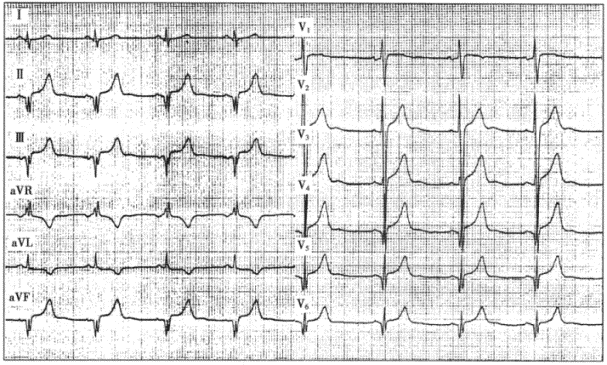

2.患者男性,40岁,扩张型心肌病。心电图如下图所示,与该心电图表现不符合的诊断是

正确答案:E 解题思路:扩张型心肌病的心电图表现常无特异性。该患者的心电图表现为:P波消失,代之以大小、形态、间距不一的f波,主导心律为心房颤动;心电轴左偏;Ⅱ、Ⅲ、aVF导联QRS波群呈QS形;R导联振幅达3.5mV,伴继发性ST-T改变,表现左心室肥大伴劳损的图形;扩张型心肌病由于心肌纤维化或传导异常,V~V导联可出现异常Q波或QS波,酷似前壁心肌梗死。